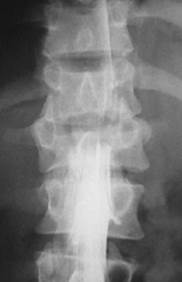

Додаткові методи досліджень. Після проведеного клінічного обстеження в діагностичний алгоритм включаються додаткові методи дослідження, що уточнюють рівень і характер пошкодження структур хребта. Діагностичний алгоритм комплексу інструментальних досліджень в гострому періоді спінальної травми починається з виконання рентгенограми (спондилограми) в двох стандартних (передньо-задній і боковій) проекціях, що дозволяє судити про наявність або відсутність пошкодження кісткових структур хребта, але не дає інформації про стан м’якотканинних утворень хребта (рис.11).

Рис. 11. Визначення ступеня компресії тіла хребця (відповідно І, ІІ та ІІІ) згідно до рентгенограми у боковій проекції

Для виявлення пошкоджень в зоні С1 – С2 хребця необхідні рентгенограми в прямій проекції через відкритий рот. Наявність неврологічних порушень і рентгенологічних ознак пошкодження кісткових структур хребта вимагає обов'язкового подальшого дослідження хребта за допомогою методу рентгенівської комп'ютерної томографії (КТ) і магнітно-резонансної томографії (МРТ), що дозволяє уточнити рівень і ступінь пошкодження спинного мозку, м'яких тканин, міжхребцевих дисків (рис. 12 а, б).